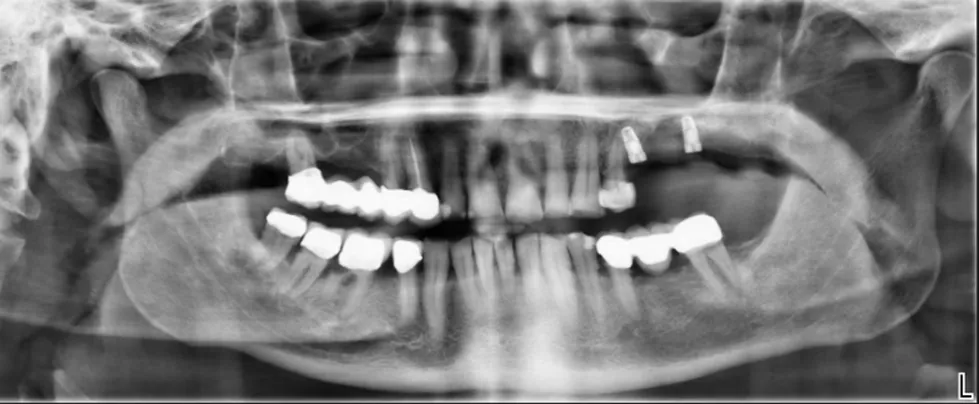

1. Diagnostische Bildgebung (DVT/CT)

Hochauflösende 3D-Daten erfassen Form, Dicke und Verlauf des Knochens – Grundlage für die Maßanfertigung.